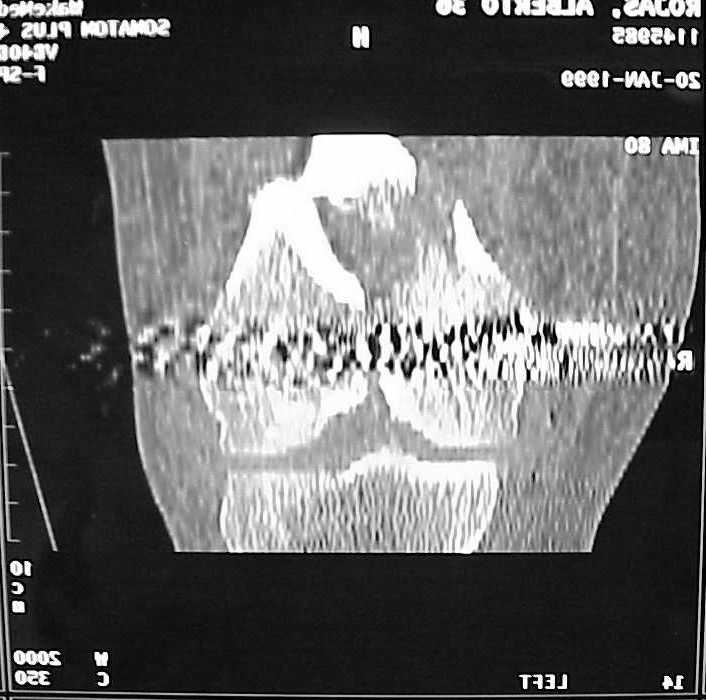

See attached case that was done several years ago before LISS. He had comminuted trochlea and anterior blocking screws were used to prevent anterior IMN cut-out.